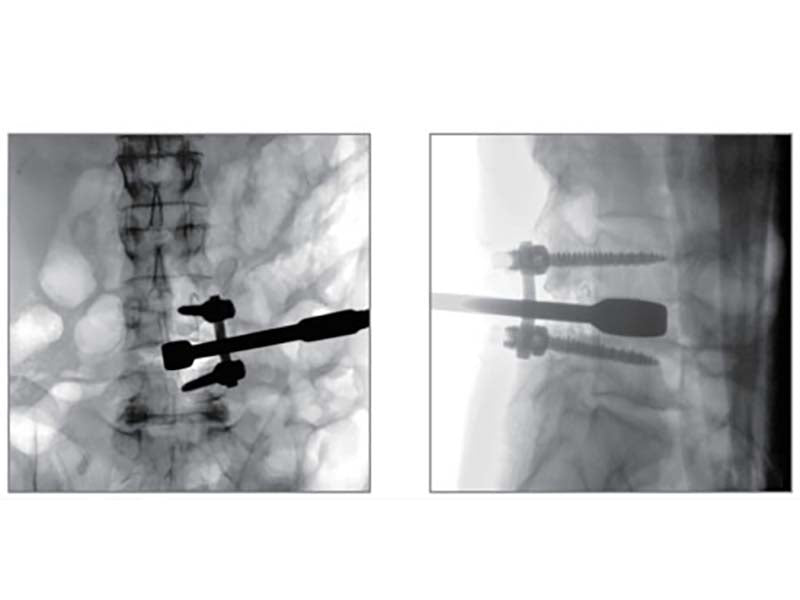

Compared to the conventional 9” image intensifier, a 9” x 9” flat panel detector is able to expand the FoV by 22%, providing more perspective for clinical diagnosis.

Higher signal coversion efficiency of FPD ensures higher image quality and lower dose.

Eliminating distorted image caused by electron beam deflection, presenting actual vision of anatomical structure.